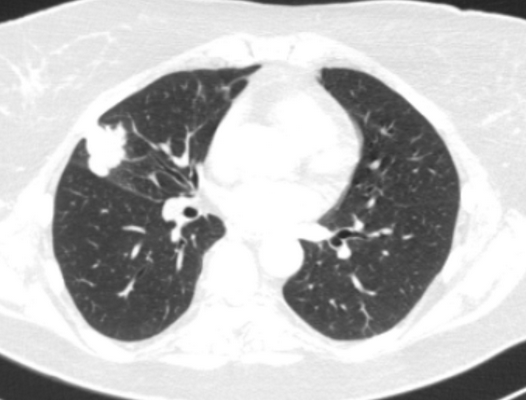

Фото 3 — Лобэктомия

Фото 4 — Пневмонэктомия

- по объему резекции (лобэктомии (удаление доли легкого), билобэктомии (удаление двух долей легкого), пневмонэктомии (удаление целого легкого)),

- по наличию резекции соседних органов и структур (комбинированные операции проводятся при прорастании опухоли в перикард, трахею, верхнюю полую вену, пищевод, аорту, предсердие, грудную стенку, позвоночник). Помимо оперативного лечения возможно применение комплексного подхода, включающего лучевую и химиотерпию.

При лечении местнораспространенного злокачественного образования с переходом на главный бронх и лёгочную артерию, в тех случаях, где раньше единственным вариантом оперативного лечения являлась пневмонэктомия, сейчас возможно выполнение органосохранных операций. В этом случае иссекается пораженный участок главного бронха с последующим восстановлением непрерывности (бронхопластические и ангиопластические лобэктомии)

Фото 5 — Схема верхней бронхопластической лобэктомии